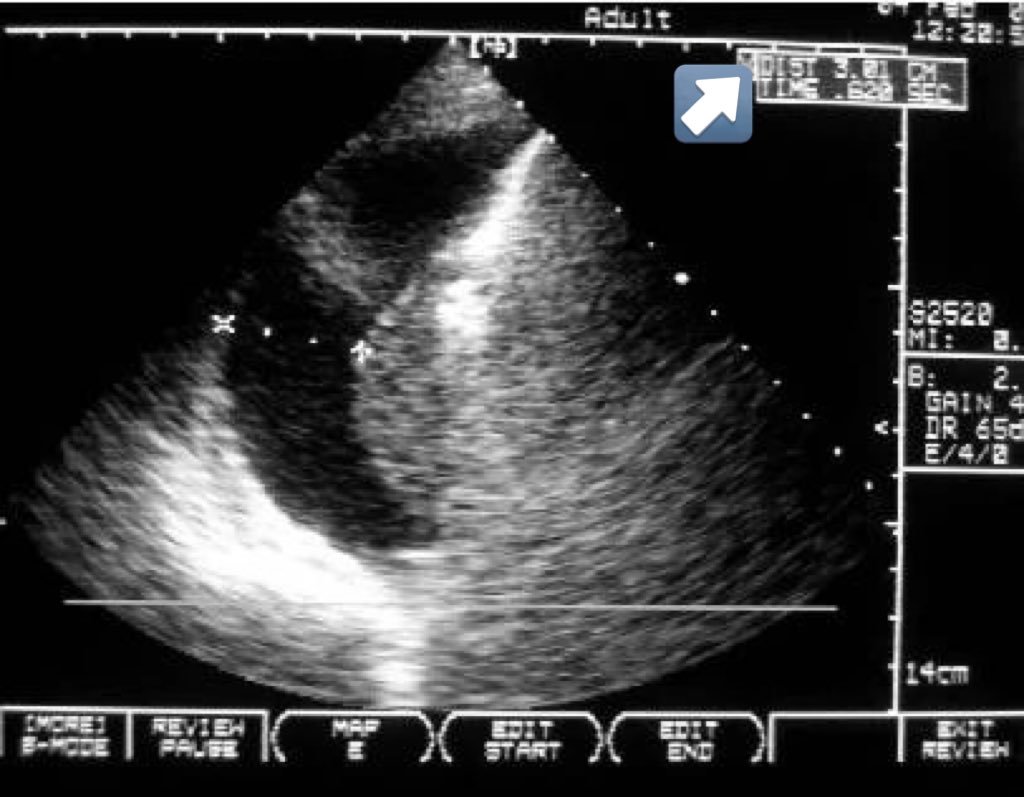

Unilateral Diaphragmatic Dysfunction secondary to phrenic nerve compression from intrathoracic mass #FOAMed #foam #MedTwitter #ultrasound